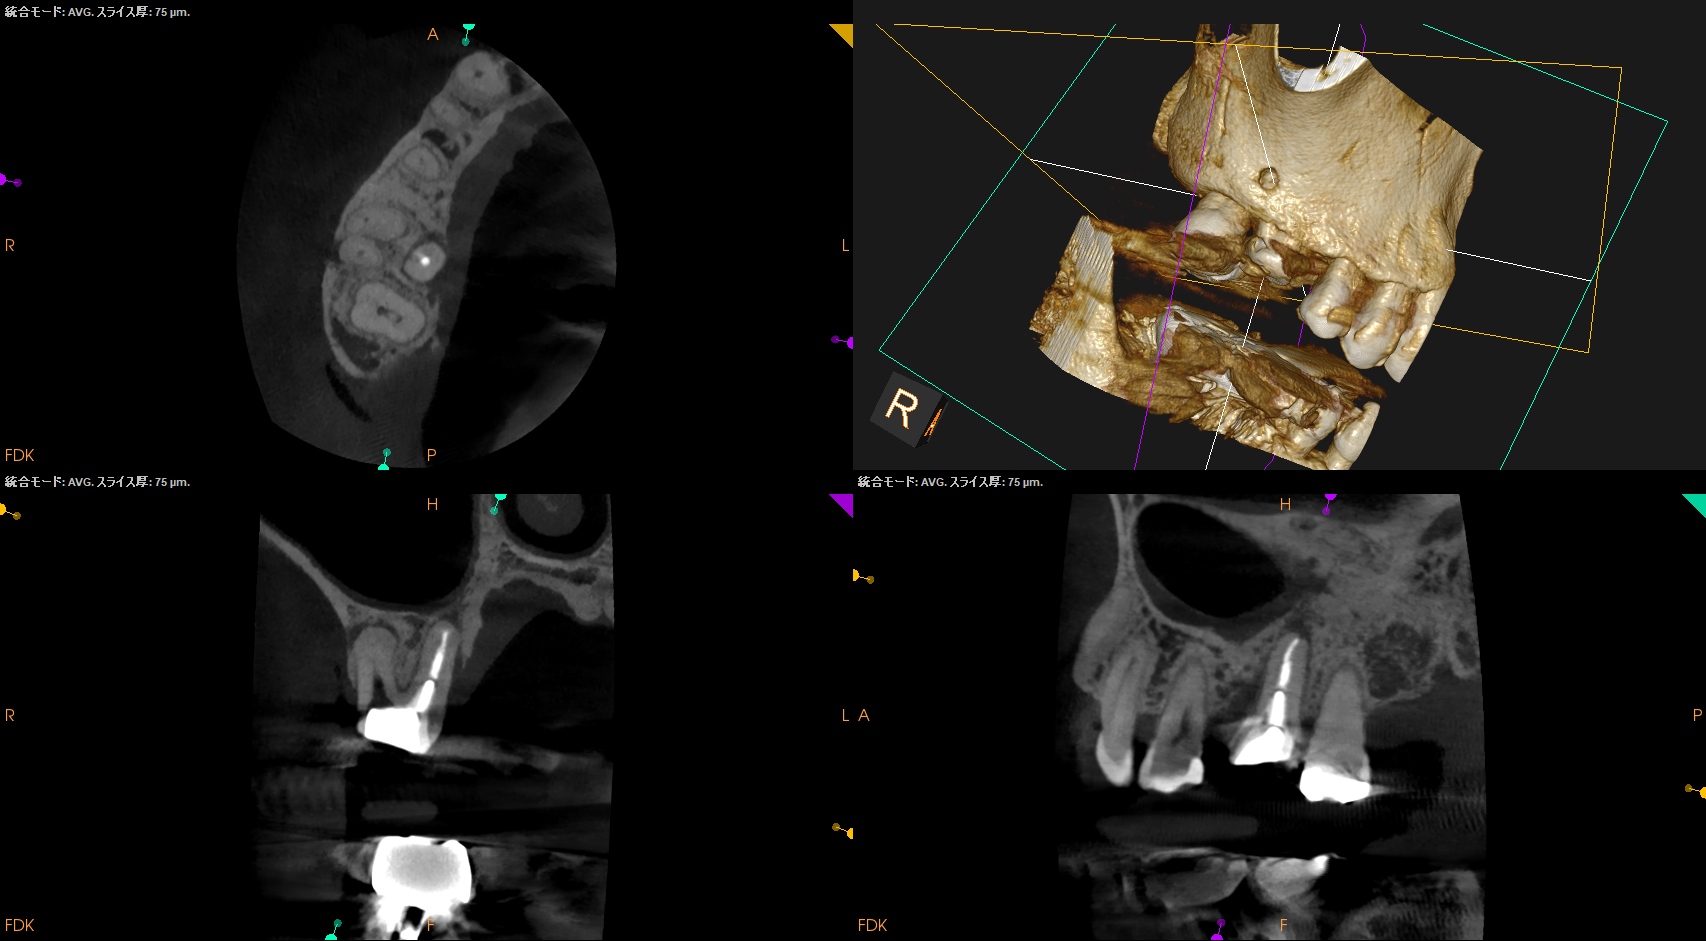

MB,DBのApicoectomyは

MB

CEJよりも12mm下方にMBのApexがあり、

そこを3mm切断するには6.4mmの切断幅が必要である。

そしてMB1-MB2を往復でPrepする必要があり、やや煩雑だ。

中程度の難易度だろう。

DB

DBはCEJよりも10.5mm下方にApexがあり、そこを3mmで切断するには5mmの頬舌的幅が必要で1根管なことからここはEasyだ。

#3 MB, DB Apicoectomy 7M recall(2026.3.30)

P

B

7ヶ月前と比較した。

劇的に歯槽骨の開創は回復している。

そしてP根だが、根尖病変の治癒とともに口蓋側の骨欠損が大きく回復しているのがわかる。